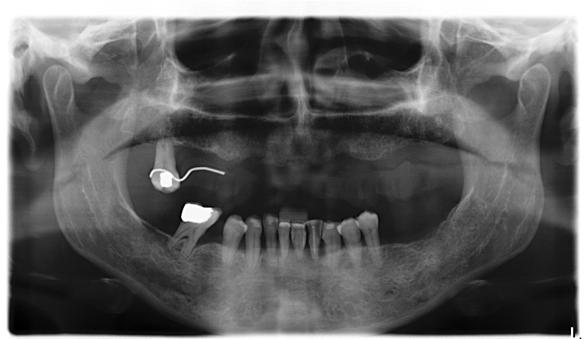

Figura 1. Radiografía inicial de la paciente. Se observa edentulismo total superior, a excepción del molar del primer cuadrante, indicado para exodoncia. En la mandíbula se aprecia pérdida ósea horizontal generalizada secundaria a la evolución de la enfermedad periodontal.

En la radiografía inicial (Figura 1) se observa la pieza 17 con pérdida ósea significativa, así como una reabsorción ósea homogénea a lo largo de todo el arco superior. En la arcada inferior se aprecia pérdida ósea horizontal generalizada y defectos localizados, como una lesión en cuña en la pieza 46. Ante esta situación, se decide realizar la exodoncia del molar remanente del